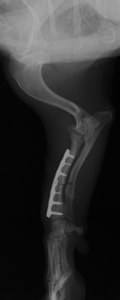

■ミニチュアダックスフント 1歳 去勢オス

前肢の成長板早期閉鎖、前肢の重度の外反変形が認められました。

関節面の変形が重度に認められます。